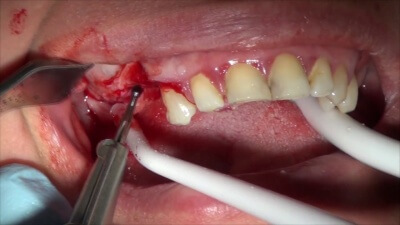

Клиническое течение послеоперационного периода у пациентов оценивалось на 3; 5 и 7 сутки после операции. На третьи сутки после оперативного вмешательства больные исследуемой группы [19 человек] отмечали отсутствие температурной реакции и болевого синдрома. Объективно: отек мягких тканей выражен слабо у 17 больных, а у 2 пациентов — отсутствовал совсем. В контрольной группе (21 человек) послеоперационный период протекал с подъемом температуры тела, выраженным отеком мягких тканей, больные отмечали необходимость приема обезболивающих препаратов. У трех пациентов контрольной группы на 3 сутки отмечается наличие гнойно-сукровичного отделяемого из линии швов, резко выраженный отек мягких тканей. Этим пациентам проведено дополнительное вмешательство, удалены швы, слизисто-надкостничный лоскут введен в костную полость, дальнейшее ведение — по типу цистотомии (под йодо-формным тампоном). По результатам рентгенологического обследования можно судить о состоянии костной ткани у пациентов до и после оперативного вмешательства. На ортопантомограмме больного С. до операции (рис. 2) определяется в области корня 37 зуба разрежение костной ткани с четкими контурами, размером 2,0 х 2,0 см., контуры нижнечелюстного канала не прослеживаются. Учитывая отсутствие костной ткани на протяжении 1/2 корня, 37 зуб в ходе операции был удален. Рис.2 Ортопантомограмма больного С. до операции  После удаления оболочки кисты костная полость заполнена препаратом "Остеоматрикс" (рис. 3). Рис.3 Препарат "Остеоматрикс" заполнен дефект ничней челюсти до границ костной полости

После удаления оболочки кисты костная полость заполнена препаратом "Остеоматрикс" (рис. 3). Рис.3 Препарат "Остеоматрикс" заполнен дефект ничней челюсти до границ костной полости  На контрольной рентгенограмме, сделаной через 1 месяц после операции, костный дефект выполнен трабекулами, наметились контуры нижнечелюстного канала (рис. 4), что свидетельствует о наличии молодой костной ткани. Рис.4 Ортопантомограмма больного С. через 1 месяц после операции